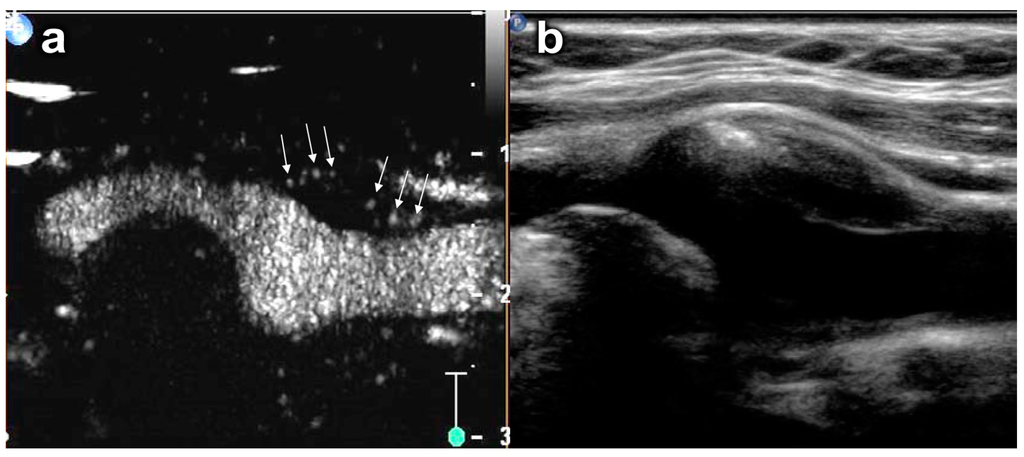

- Saito, K.; Nagatsuka, K.; Ishibashi-Ueda, H.; Watanabe, A.; Kannki, H.; Iihara, K. Contrast-enhanced ultrasound for the evaluation of neovascularization in atherosclerotic carotid artery plaques. Stroke 2014, 45, 3073–3075. [Google Scholar] [CrossRef] [PubMed]

- Ten Kate, G.L.; Renaud, G.G.; Akkus, Z.; van den Oord, S.C.; ten Cate, F.J.; Shamdasani, V.; Entrekin, R.R.; Sijbrands, E.J.; de Jong, N.; Bosch, J.G.; et al. Far-wall pseudoenhancement during contrast-enhanced ultrasound of the carotid arteries: Clinical description and in vitro reproduction. Ultrasound Med. Biol. 2012, 38, 593–600. [Google Scholar] [CrossRef] [PubMed]

- Renaud, G.; Bosch, J.G.; Ten Kate, G.L.; Shamdasani, V.; Entrekin, R.; de Jong, N.; van der Steen, A.F. Counter-propagating wave interaction for contrast-enhanced ultrasound imaging. Phys. Med. Biol. 2012, 57, L9–L18. [Google Scholar] [CrossRef] [PubMed]